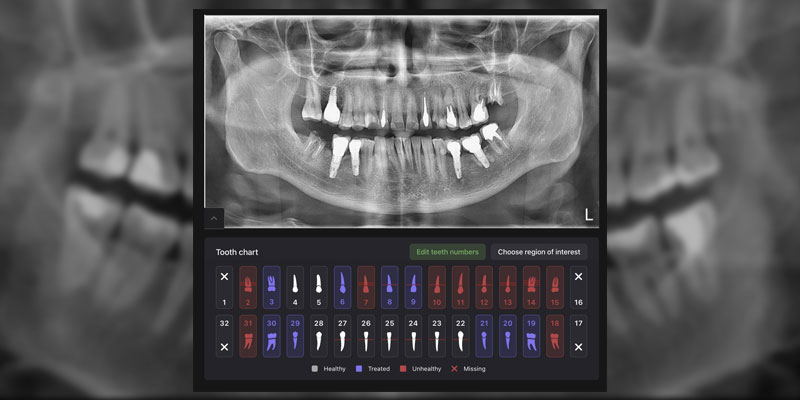

Искусственный интеллект Diagnocat

Первичная консультация с искусственным интеллектом Diagnocat

1823

Используем Diagnocat